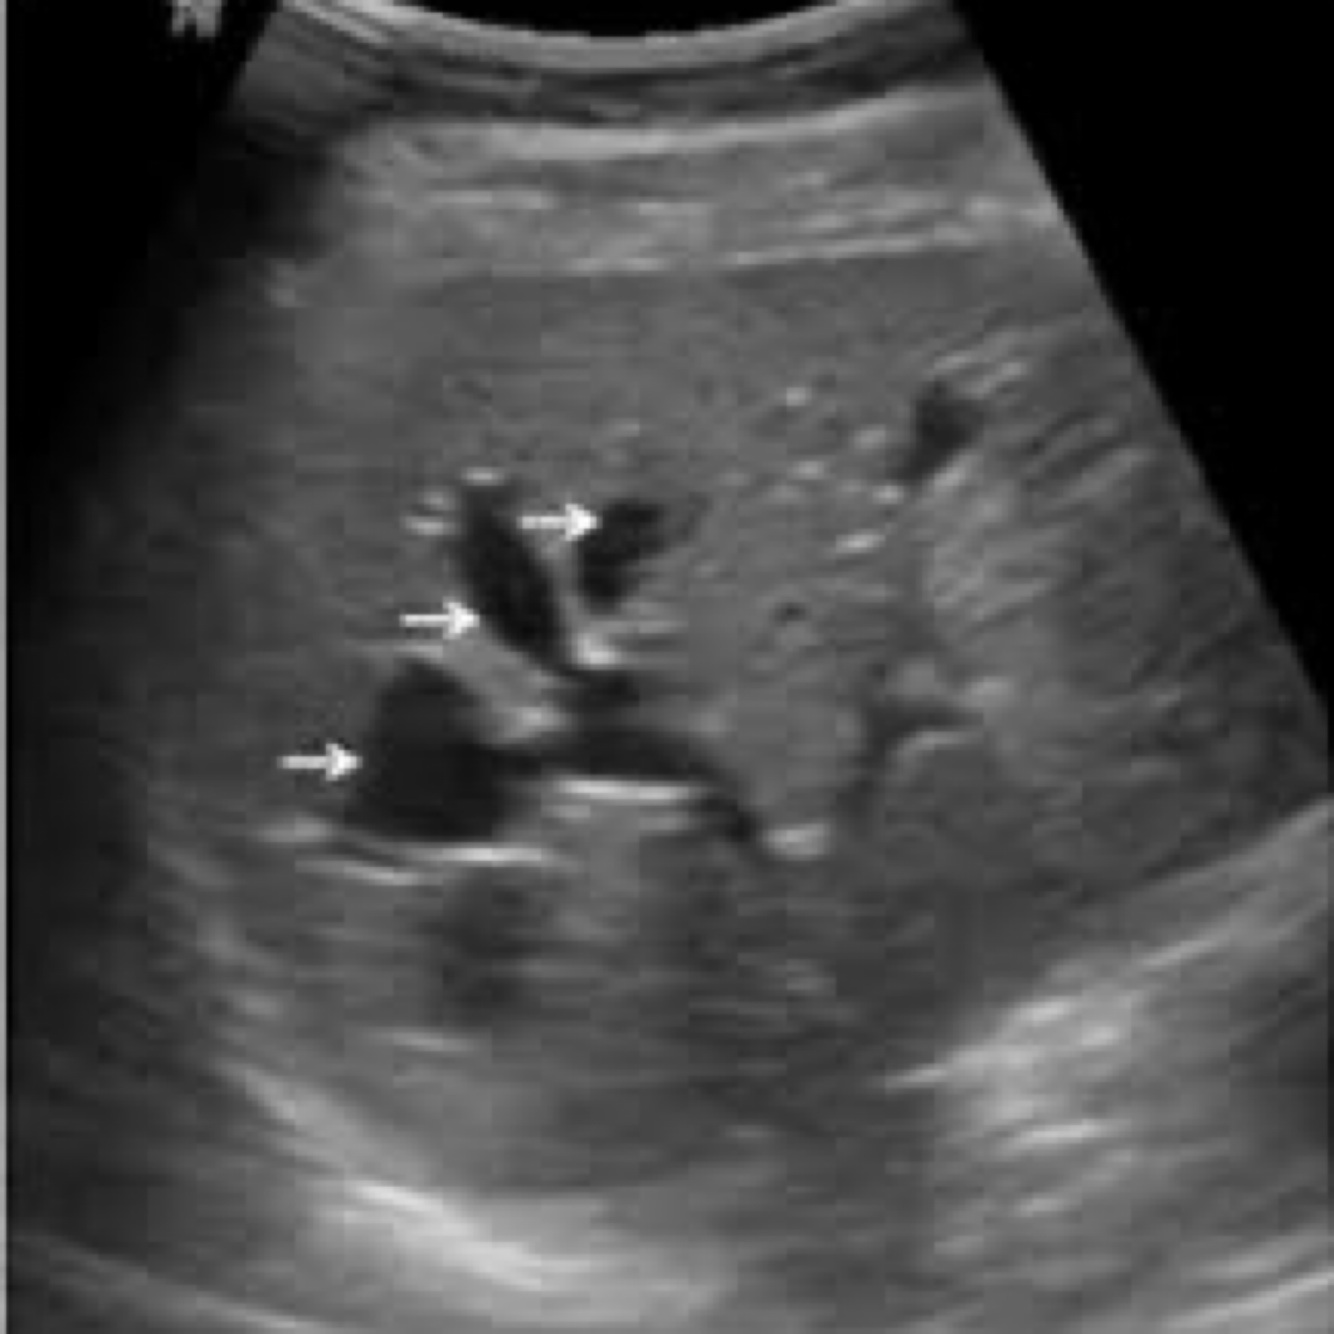

Caroli disease: is a rare, congenital condition characterized by dilatation of the intrahepatic bile ducts, leading to the formation of cystic structures within the liver.